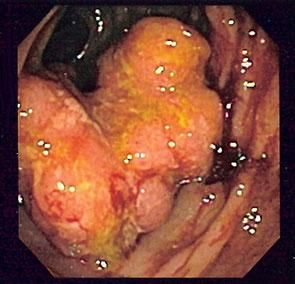

Tiny cameras that can see inside the body and, along with blood tests, CT scans and MRI, are used to detect cancers forming inside the body

(Photo credit: Dcoetzee, Wikimedia Commons)

Sometimes the tumours grow deep inside the body. If there is plenty of room for them to grow before they cause symptoms, they can easily become very big and have formed many metastases before the person affected becomes aware of the problem. This may occur with lung cancers, stomach cancers and bowel cancers for example.